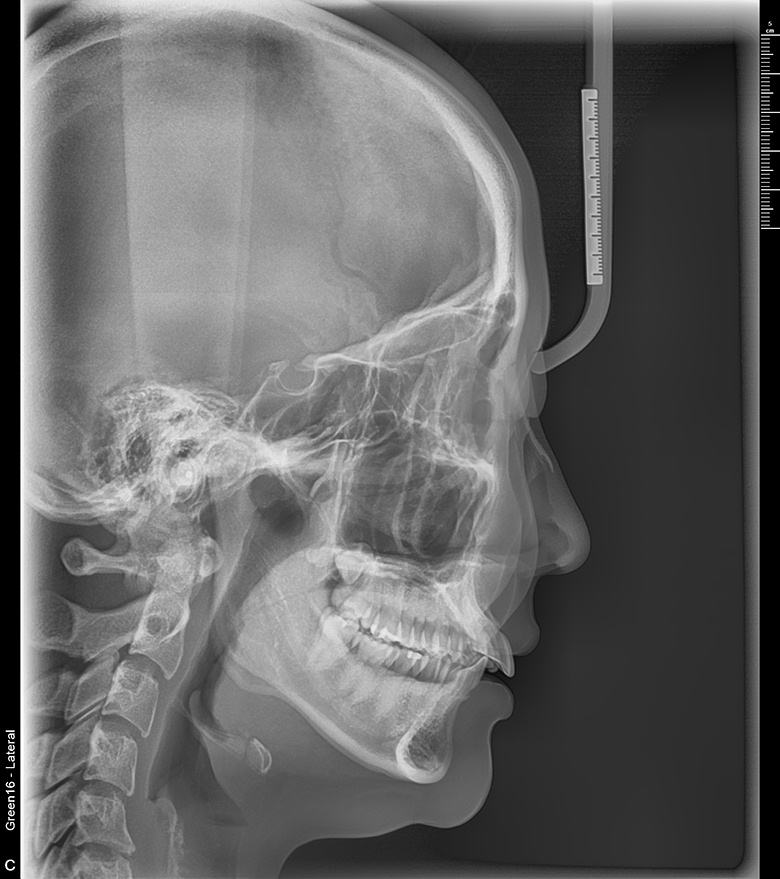

치료 후 사진입니다.